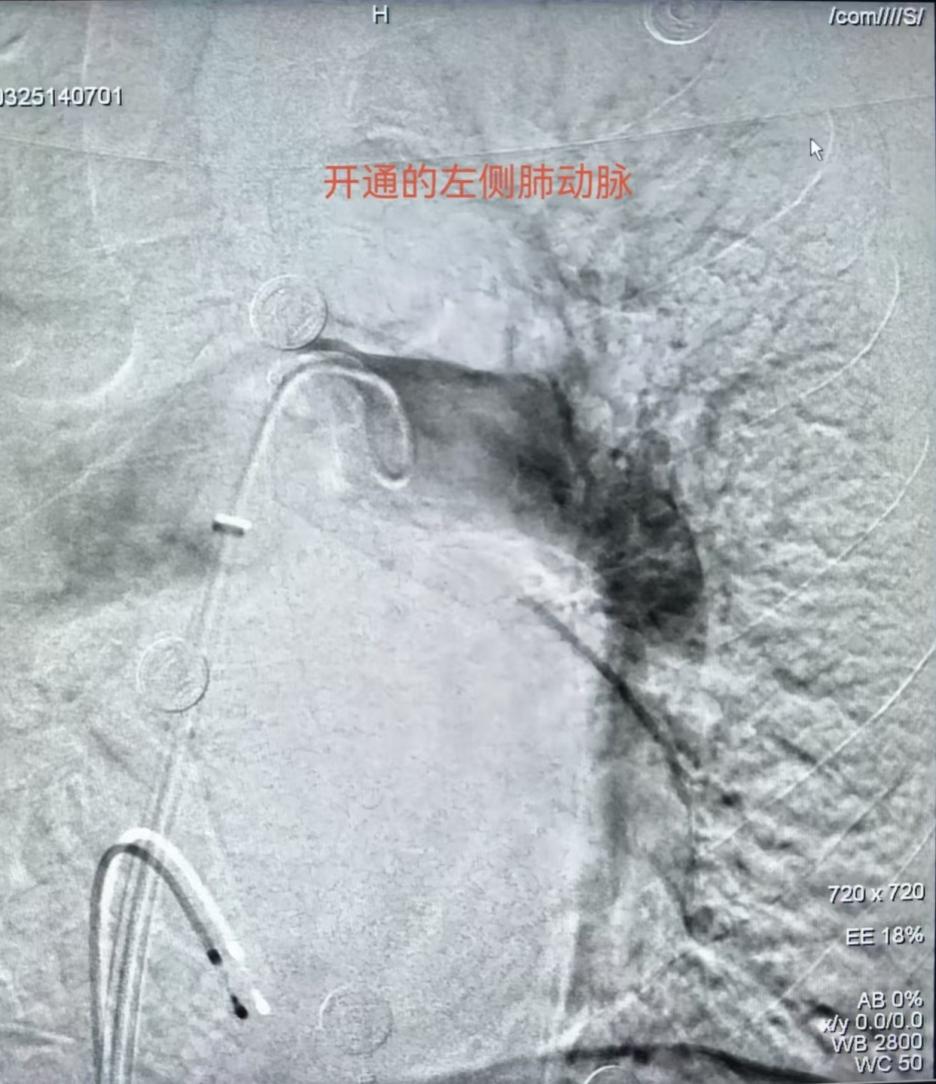

面对突发状况,护理人员沉着冷静,迅速配合医生完成左股静脉穿刺并置入临时起搏器,经测试起搏效果良好,患者心率成功恢复并维持在80次/分,为后续取栓操作创造了安全的身体条件。在血栓抽吸的关键环节,护理人员精准递送各类专用器械,密切配合医生开展双侧肺动脉血栓抽吸操作,成功抽出大量红、白色血栓。操作过程中,护理人员持续严密监测患者生命体征变化,根据手术需要及时追加肝素钠注射液进行抗凝处理、补充碘造影剂,全程保障手术安全、高效推进。

术后造影显示,患者双肺动脉充盈缺损情况明显改善,肺部血流灌注恢复良好。术中抽取的约400ml血液,经专业过滤去除血栓后,护理人员协助医生全部回输给患者,有效维持了患者的循环稳定。手术结束后,护理人员严格按照拔管后护理规范,对患者穿刺部位进行加压包扎,术后持续严密观察患者下肢血运情况,做好各项基础护理工作。